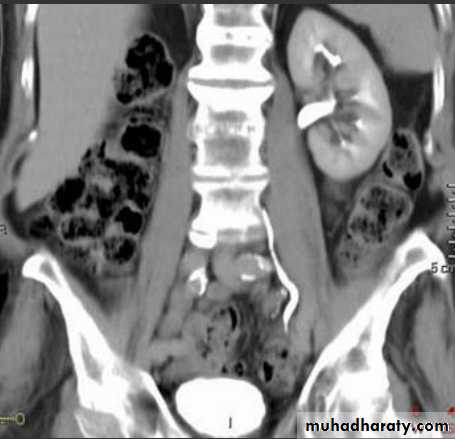

Normal CT scan of abdomen

CT scanstones in kidneys

High density renal stonesStage horn calculus KUB filmsradio opaque stones